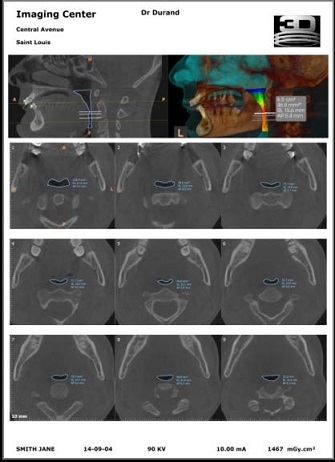

Misurazioni automatizzate

Per ciascuna figura di segmentazione, il modulo CS Airway calcola e individua automaticamente:

• il volume totale in mm3

• l'area minima cross-sezionale in mm2

• la distanza antero/posteriore (A/P) minima in mm

• la distanza destra/sinistra (R/L) minima in mm

Misurazioni dinamiche

Le misurazioni di qualsiasi sezione nel piano assiale sono visualizzate automaticamente e aggiornate in modo dinamico mentre l'utente naviga con la sezione.